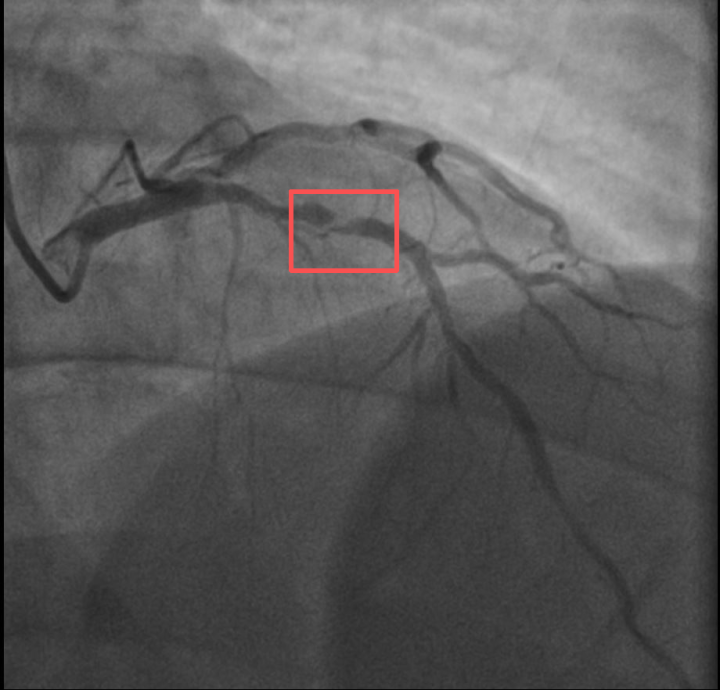

介入治疗前影像图

浙江医院心血管内科的医生分析,剧烈运动导致这位患者心脏的不稳定斑块破裂,进而造成前降支近段次全闭塞。所幸送医及时,孙先生的身体险情被化解。